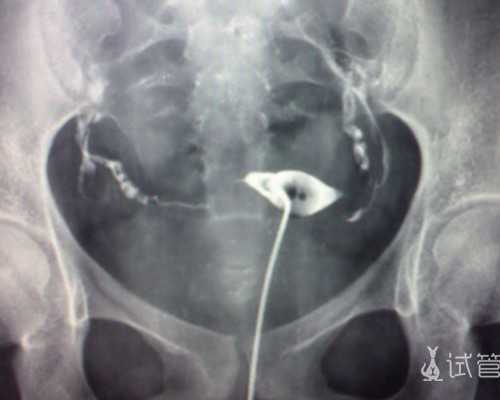

促排后期不建议同房,促排后期卵泡生长较快,卵泡多而大,如果同房有可能会发生卵巢扭转等不适情况,不仅可能导致取卵失败,还有可能卵巢缺血坏死。

3促排卵后不建议同房因为此阶段女性卵巢会受到药物的刺激,特别是在促排卵后期,由于多枚卵泡的生长,卵巢体积变大,此时同房,可能会增加卵巢扭转的风险,造成卵巢血供不足,严重者需要切除一侧卵巢。

而且促排卵后期,部分卵泡已成熟,若是情到深处,难免容易激动,但这很有可能促使成熟卵泡排卵,在取卵时取不到卵子,所以此阶段不建议同房。